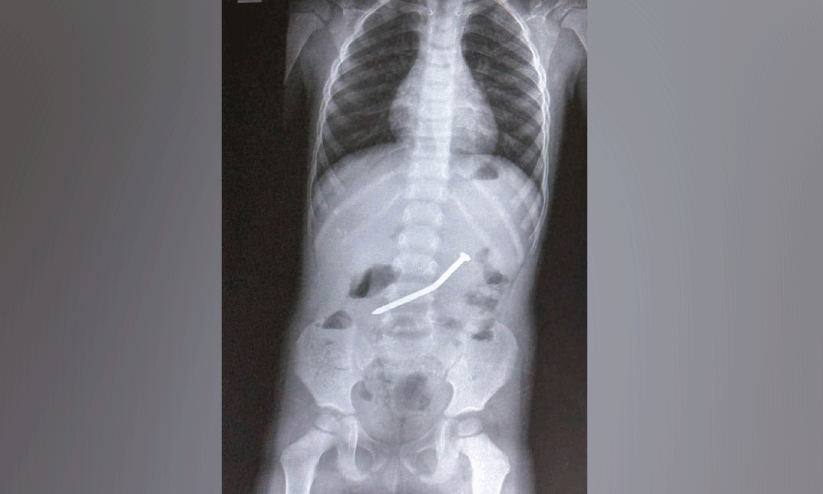

text_fieldsകുട്ടിയുടെ ചെറുകുടലിൽ രണ്ടര ഇഞ്ച് നീളമുള്ള ആണി

മേപ്പാടി: മുട്ടിൽ കുട്ടമംഗലം സ്വദേശികളായ ദമ്പതിമാരുടെ രണ്ടര വയസുകാരന്റെ വയറ്റിൽ അകപ്പെട്ട രണ്ടര ഇഞ്ച് നീളമുള്ള വണ്ണം കൂടിയ ഇരുമ്പാണി വിജയകരമായി പുറത്തെടുത്തു.ഡോ. മൂപ്പൻസ് മെഡിക്കൽ കോളജ് ഉദര-കരൾ രോഗ വിഭാഗം (ഗാസ്ട്രോ എന്ററോളജി) സീനിയർ സ്പെഷലിസ്റ്റ് ഡോ.ടി. ശ്രീനിവാസ് റെഡ്ഢിയാണ് ചെറുകുടലിന്റെ തുടക്ക ഭാഗത്ത്(ഡിയോഡിനം) കുത്തി നിന്ന ആണി എൻഡോസ്കോപ്പിലൂടെ പുറത്തെടുത്തത്.

വീട്ടിൽ കളിച്ചു കൊണ്ടിരുന്ന കുട്ടി കൈയിൽ കിട്ടിയ ആണി വിഴുങ്ങുകയായിരുന്നു. ഇത് കണ്ട മൂത്ത കുട്ടിയാണ് മാതാപിതാക്കളോട് വിവരം പറഞ്ഞത്. പിന്നീട് പനിയുടെ ലക്ഷണങ്ങളോടെ കൽപ്പറ്റ ജനറൽ ആശുപത്രിയിൽ പ്രവേശിപ്പിച്ച കുട്ടിയുടെ എക്സ്റേ വീണ്ടുമെടുത്തപ്പോൾ നേരത്തേ കണ്ട സ്ഥലത്തുനിന്നും ആണിയുടെ സ്ഥാനം മാറാത്തതിനെ തുടർന്ന് വിദഗ്ധ ചികിത്സക്കായി ഡോ. മൂപ്പൻസ് മെഡിക്കൽ കോളജിലേക്ക് അയക്കുകയായിരിന്നു.